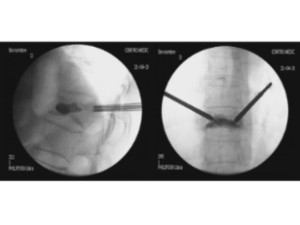

Estabilización percutánea de fracturas vertebrales inestables

En casos de fracturas vertebrales complejas, inestables, conminutas, etc. se requiere una estabilización adicional de la fractura mediante una artrodesis percutánea, y en algunos casos en los que hay compromiso neurológico, una descompresión del canal medular. La artrodesis percutánea permite estabilizar la estrctura comprometida de la columna vertebral y descargar la carga del paciente sobre la fractura. Adicionalmente se suelen cementar las vertebras artrodesas y la fractura vertebral mediante cifoplastia.

Caso clínico con estabilización percutánea de fractura vertebral inestable.